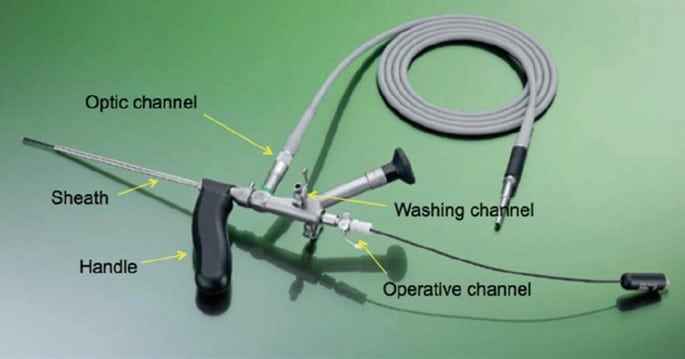

Το σημαντικότερο ίσως πλεονέκτημα των MITs είναι ότι προστατεύουν τον έσω και έξω σφιγκτήρα του πρωκτού. Τεχνικές όπως η FiLaC™ (Fistula Laser Closure), η VAAFT (Video-Assisted Anal Fistula Treatment) και η LIFT (Ligation of the Intersphincteric Fistula Tract) έχουν σχεδιαστεί ώστε να αποφεύγουν τη διατομή των σφιγκτήρων, μειώνοντας τον κίνδυνο ακράτειας στο ελάχιστο.